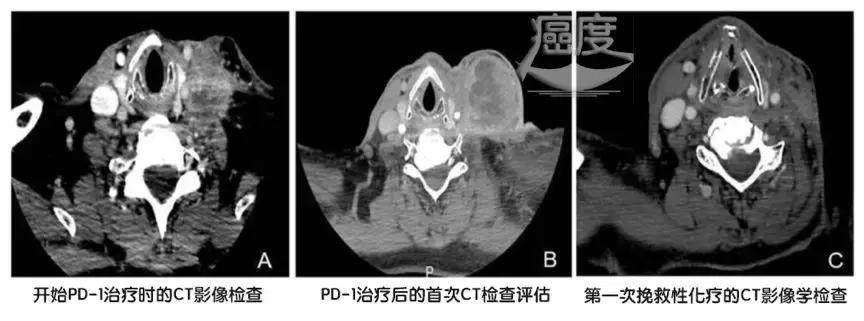

2017年7月病情再次进展,这个时候开始使用PD-1的O药,也就是纳武利尤单抗,每15天一个疗程,使用的剂量为每公斤体重3毫克。4个治疗周期后,病情还是进展了,也就是PD-1的4个周期没有压制住病情。不得已病人开始使用紫杉醇化疗。3个月之后,病人的病情出现意想不到的应答,病情获得了显著缓解,如下图所示。